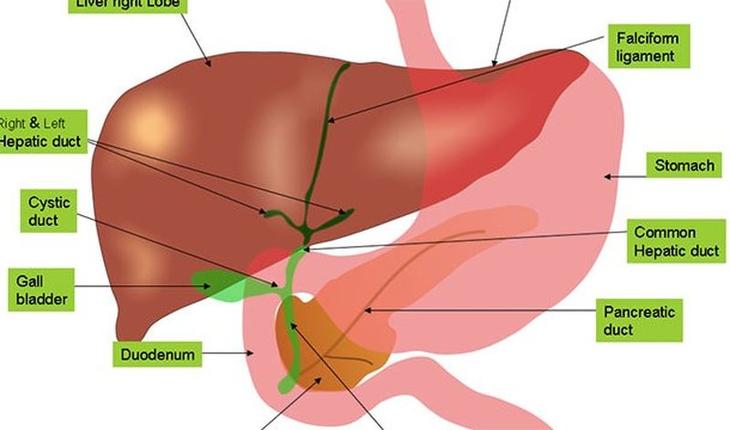

7) К слову о жизненно важных органах – они тоже отличаются. И речь не о признаках пола, как многие могли бы подумать. Одно из отличий кроется в печени: около 1000 генов, которые варьируются в зависимости от пола, связаны с работой печени. Именно поэтому все, что перерабатывается с её участием, перерабатывается с разной скоростью.